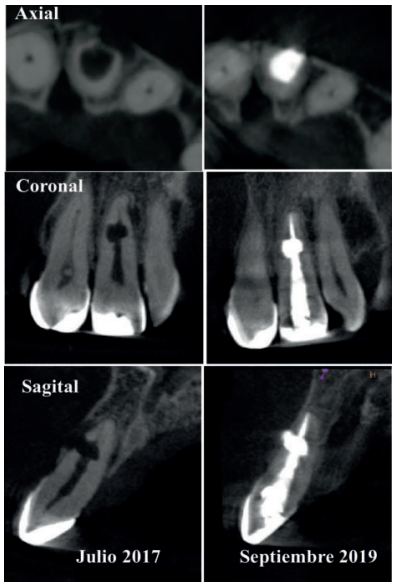

Se realizó un 3D a los 26 meses para una nueva evaluación de la zona reabsortiva, y así evaluar el estado óseo alrededor de la misma. La paciente se presenta totalmente asintomática sin signos clínicos y con buena salud de los tejidos periapicales.

Se realiza un CBCT de campo pequeño con un voxel de 75 micras. A través de las pruebas complementarias, estudio radiográfico y análisis de la literatura llegamos al diagnóstico de reabsorción interna inflamatoria perforante (Figura 2).

Se realizaron revisiones a los 6, 12, 18 y 26 meses, encontrándose la paciente totalmente asintomática, con signos de curación en los tejidos periapicales, observándose una regeneración ósea completa en la cortical vestibular (ausente en radiografia inicial). A los 26 meses se le dio el alta y se remitieron al referidor todas las pruebas diagnósticas y radiológicas (Figura 7).

A los 26 meses la paciente se presenta asintomática y con signos de curación de los tejidos periapicales, observando una aposición ósea sobre el material biocerámico, poniendo de manifiesto la tolerancia del MTA con los tejidos periapicales.